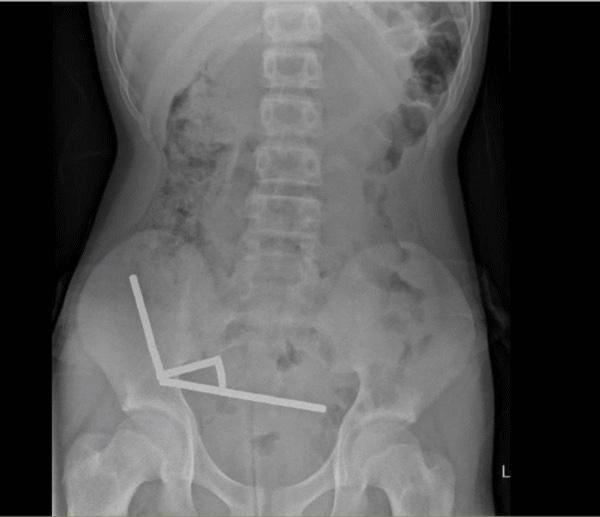

X光中顯示,這些小磁鐵在他腸子裡的不同部位中形成4條鏈子互相拉扯,並切斷了附近組織的血流,壓力更導致多處壞死。